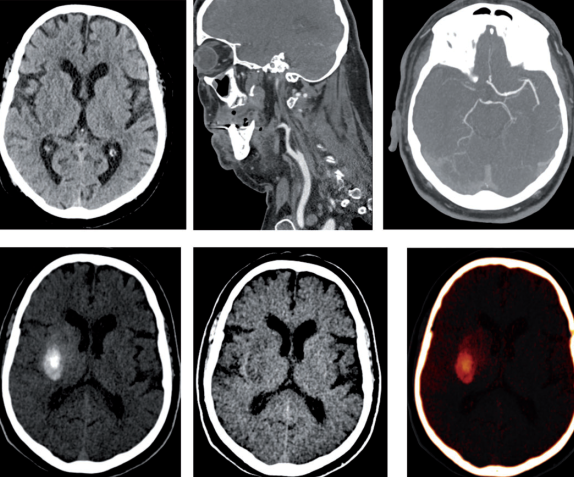

该高端CT在国内外具有先进的技术特点,主要体现在:时间分辨力成倍提升;发明了心脏前瞻性螺旋扫描模式;开创了超级炫速扫描模式;能谱纯化技术创新应用;大范围动态灌注与4D CTA成像。该设备目前在脑卒中、胸痛(冠脉、心肌病变)、创伤(骨骼、骨髓病变)、小儿胸部扫描(自由呼吸)、心脏成像、抑制内固定金属伪影、非钙化性胆结石检出、淋巴瘤和淋巴结转移的鉴别、化疗栓塞后疗效评估、尿路结石定性分析、乳腺假体评估等方面优势显著。